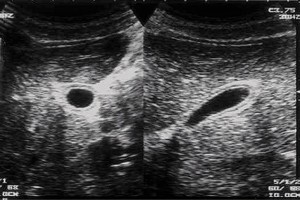

Diplomados en Ultrasonografía